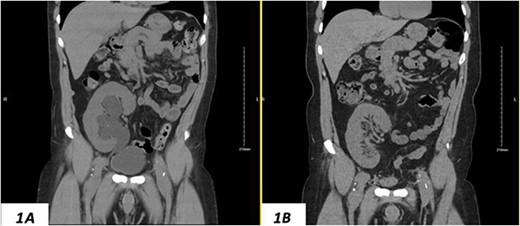

Despite a new onset proteinuria of 50 mg/dl, he continued to have a good functioning graft with a creatinine level of 93 μmol/l corresponding to an estimated glomerular filtration rate (eGFR) of 78 ml/min/1.73 m2. Nonetheless, he had also been noting an inguinal bugle that becomes more prominent as the day progressed, and it regressed at night. Upon further investigations, an ultrasound of the allograft revealed moderate-to-severe hydronephrosis. Further imaging using computed tomography scan (CT) confirmed the presence of upstream moderate hydronephrosis (Figs 1A and2A) along with a reported herniation of the ureter in a right inguinal hernia, resulting in a focal distal ureteric dilatation of 3.5 cm (Fig. 3A).

(A) Hydronephrosis of the allograft ureter on preoperative cross-sectional CT scan; (B) significant improvement of hydronephrosis on the 10-month postoperative image.